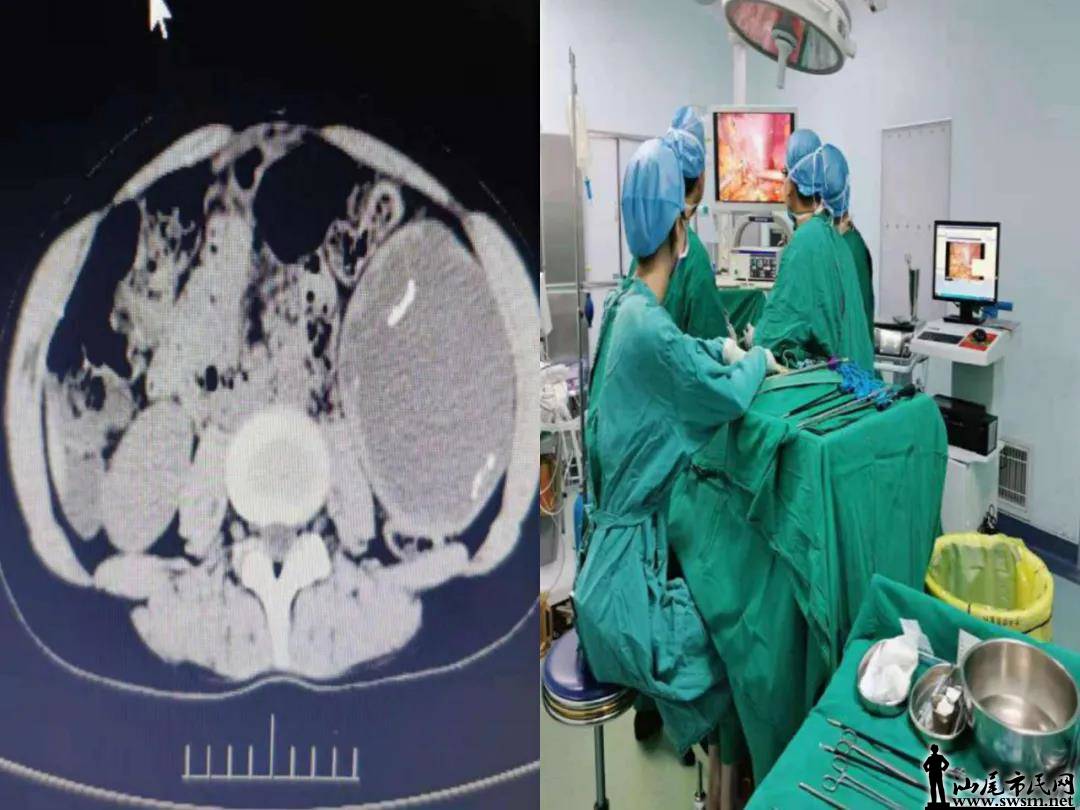

近日,我院普外科收治一名脾淋巴管瘤(多发囊性病灶)的患者,予行腹腔镜下脾切除术,术后快速恢复,而且整个过程舒适感明显,完全改变了患者原来认为的手术是痛苦、恐怖和危险的观点。据普外科副主任石一峰介绍,患者这截然不同的体验主要是因为加速康复外科理念的应用带来的。术前6小时禁食,术前2小时还可以喝水;手术过程中不留尿管;手术摒弃过程大切口创伤大的方式,而是用腹腔镜微创手术;术后6小时该患者开始喝水,术后第一天开始流质饮食,整个过程予镇痛状态,疼痛轻,早期就下床活动,两天拔出腹腔引流管,恢复顺利,1周后出院。

微信图片_20210521135652.jpg

微信图片_20210521135654.jpg